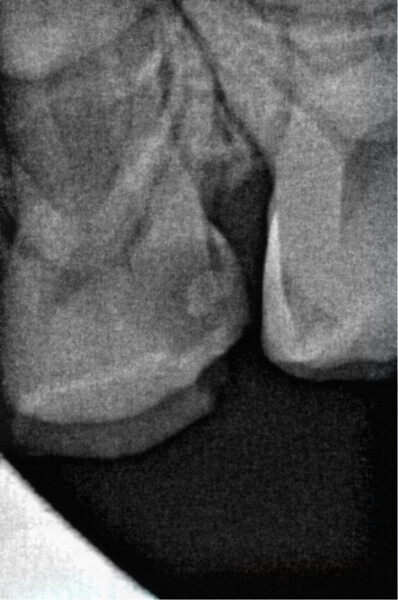

The following patient case illustrates how easy endodontic treatment can be using the Jeni. The patient was a 6-year-old boy who attended Dentiland in spring this year with complaints concerning his upper jaw. Intra-oral diagnostics confirmed the need for treatment of tooth #64 (Fig. 2), and Type II early childhood caries was diagnosed. After detailed counselling, the patient and his parents consented to root canal therapy. The endodontic treatment in this case followed the five classic steps:

Fig. 2: Pre-op radiograph of tooth #64. (Image: Dr Anne Heinz)